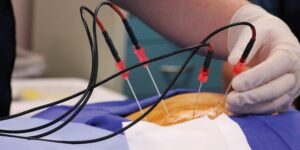

A neuroestimulação medular é um procedimento médico cirúrgico, no qual um dispositivo é implantado para fornecer estímulos elétricos controlados na

A discectomia e a descompressão percutânea são procedimentos cirúrgicos com técnicas minimamente e percutânea realizados para tratar a dor causada

A denervação das facetas por radiofrequência, também conhecida como rizotomia facetária por radiofrequência, é um procedimento médico minimamente invasivo utilizado

A rizotomia e a neurotomia por radiofrequência são procedimentos médicos minimamente invasivos realizados para tratar a dor crônica que não